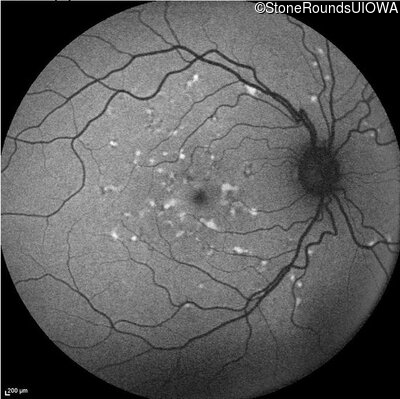

Blue Autofluorescence - Right - 20/20 -2

Exemplar